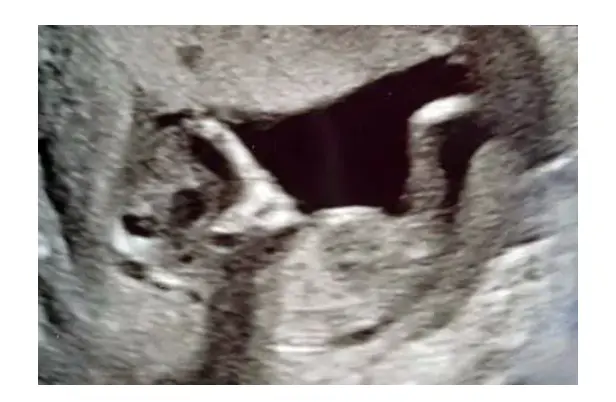

ماجرا از آن قرار است که مادری جوان در انگلیس در سونوگرافی اخیرش با صحنهای عجیب و ترسناک در رحمش مواجه شد که تصمیم گرفت آن را در فضای مجازی انتشار دهد.

سوفی اسکات ۱۶ ساله و استیفن ۲۴ ساله زمانی که برای سونوگرافی به پیش پزشک رفتند با صحنهای عجیب در شکم سوفی مواجه شدند که آنها را تاحدودی ترساند.

در شکم سوفی دو چشم عجیب و ترسناک جنین به چشم میخورد که به شدت به موجودات فضایی شباهت دارد به همین منظور موجب ترس و وحشت آنها شده است.

به گفته سوفی: من ترسیدم که این موجود بیگانه جنین من را خورده باشد و این چشمان چشمهای یک موجود فضایی به جای دخترم در شکمم باشد.